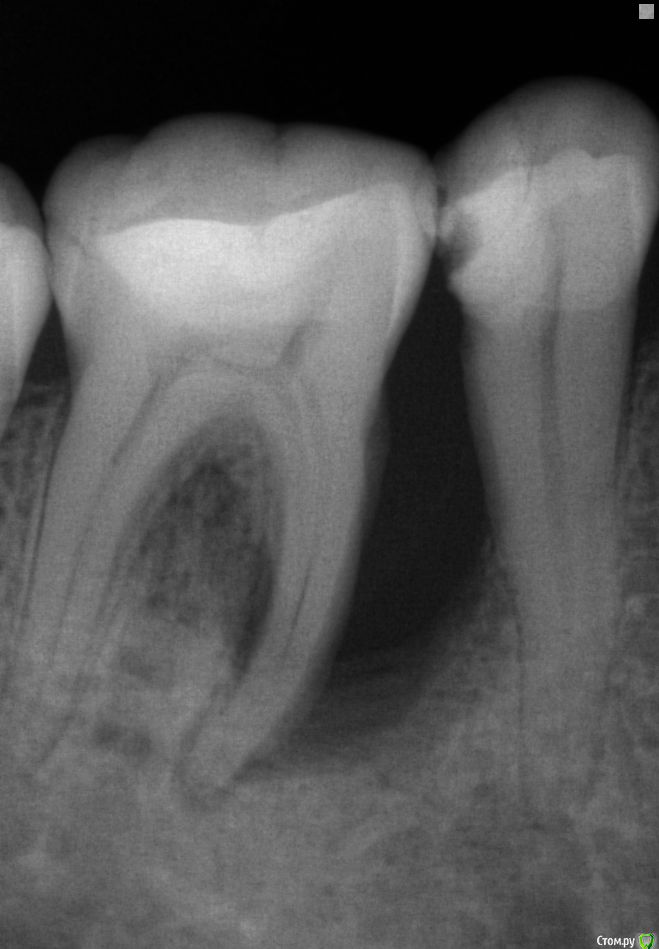

Zolotoy255 Опубликовано 16 июля, 2018 Поделиться Опубликовано 16 июля, 2018 (изменено) Пациентка 44 года , жалобы : гноетечение из кармана . Выполнен открытый кюретаж , лоскут уложен обратно в дефект заброшен PRF в связи с дефицитом слизистой. Исходное состояние слизистая в области 4.6,.4.5 держится в области шеек данных зубов. Рецессии пока нет. Вторые сутки после кюретажа жалоб нет , всё спокойно. Вопрос собственно в следующем , пациентка очень не хочет расставаться с зубами кто то выводил подобные случаи или эта бессмысленная трата времени? Поделитесь мыслями и опытом. Заранее спасибо. Изменено 16 июля, 2018 пользователем Zolotoy255 Ссылка на комментарий

krokomot Опубликовано 16 июля, 2018 Поделиться Опубликовано 16 июля, 2018 такой глубокий карман, при удовлетворительном состояни остального пародонта, может говорить о трещине корня, обязательно проверить на витальность зуб, и на снимке виден участок перехода воспаления на межкорневую перегородку. Выполнить кт ,проверить на витальность. 1 Ссылка на комментарий

Zolotoy255 Опубликовано 17 июля, 2018 Автор Поделиться Опубликовано 17 июля, 2018 такой глубокий карман, при удовлетворительном состояни остального пародонта, может говорить о трещине корня, обязательно проверить на витальность зуб, и на снимке виден участок перехода воспаления на межкорневую перегородку. Выполнить кт ,проверить на витальность.У пациентки пародонтит не только в этой области , много где ещё но тут самая серьезная проблема на сегодняшний день. Кроме ЭОД все проверил ,зуб сам не беспокоит. ЭОД просто нету . Жалобы были исключительно на десну и гноетечение. Вопрос именно о том есть ли шанс ликвидировать такой карман , не хотелось бы начать относительно дорогое терапевтическое лечение при том что всё за ранее обречено на провал. Я прекрасно понимаю что ситуация неоднозначная и описание данного случая как попало написано на коленке. Но если кто-то сталкивался с таким хотелось бы понять перспективы консервативного лечения. Пациентку очень ограничивают финансы а у меня обостренное патологическое чувство что всем нужно помогать и спасать Может не правильно выбрал решение? Хотел убрать острое состояние , добиться мало мальской стабильности слизистой , после чего перейти к эндо зубов и пластики кармана ?При такой схеме :1 эндо2 при необходимости повторный кюретаж3 пластика прикрепленияЕсть ли шансы? И можно ли обойтись только PRF или обязательно биоос(либо аналог) нужен? PRF бюджетный вариант и вроде как даже с него получается НКР у кого-то сделать.Резюмируя коллеги поделитесь мыслями, давайте обсудим кому не лень , очень хочется помочь человеку Ссылка на комментарий